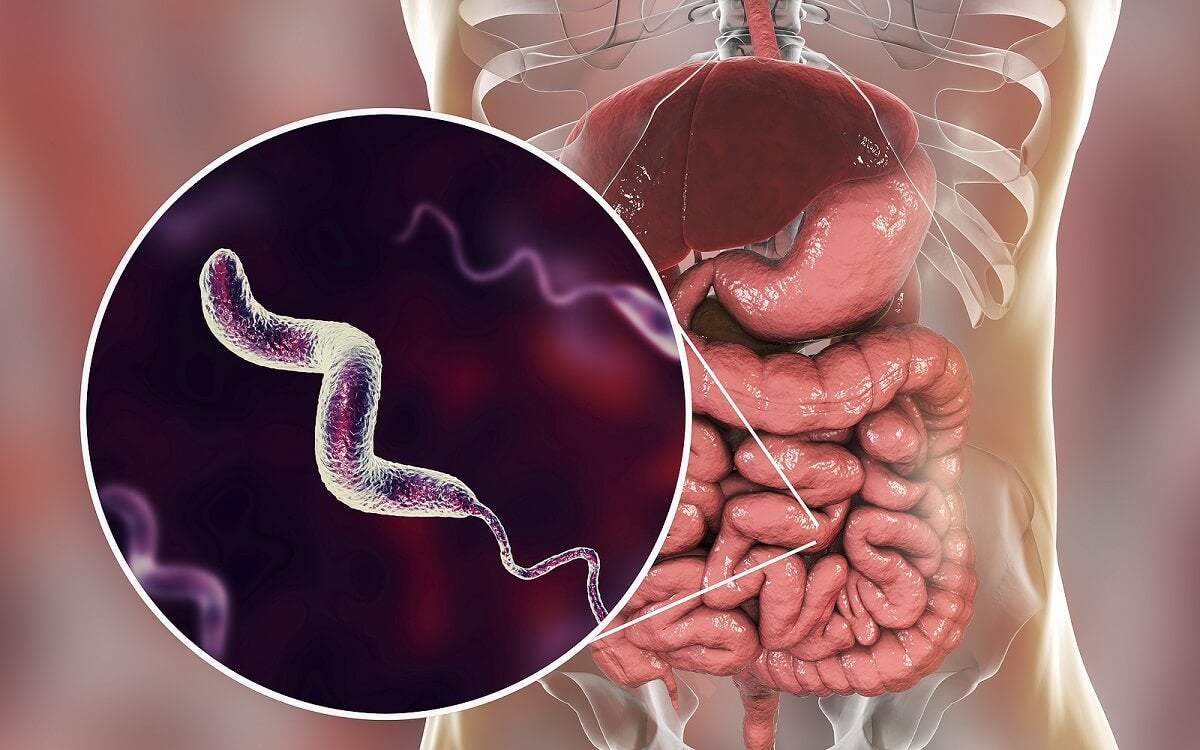

Кампилобактер фетус: патогенез и инфекции

Раздел: Другие животные